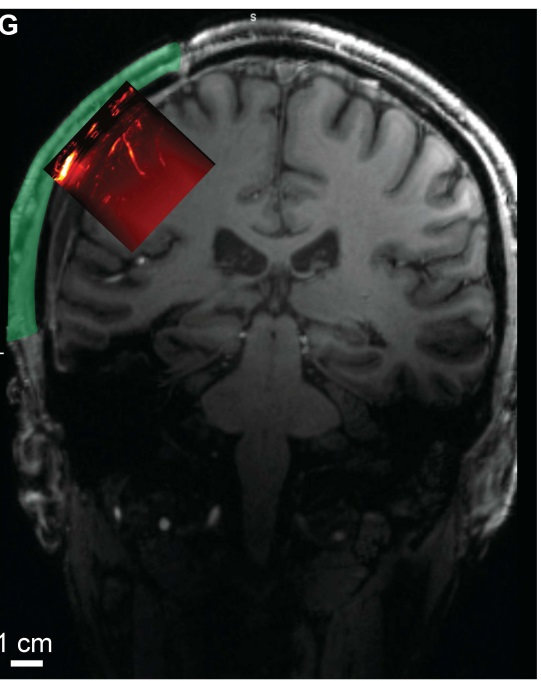

功能性超声成像平面与解剖学MRI扫描。

图片来源:《科学·转化医学》

研究团队此次创造性地克服了这一障碍,用聚合物头骨替代材料构建了一个声学“窗口”,借此能够透过人类头骨进行功能超声成像。在对大鼠进行一些初步测试后,研究团队在一名成年志愿者身上安装了一个由聚甲基丙烯酸甲酯制成的声学“窗口”。该志愿者曾在创伤性脑损伤后接受了颅骨重建手术。